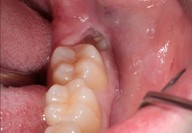

Galleria fotografica